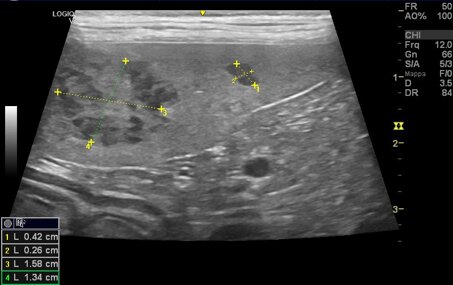

L'ecografia addominale è un esame che permette di valutare in modo non invasivo e non doloroso le condizioni degli organi situati nell'addome.

Questo esame può essere eseguito in concomitanza di condizioni cliniche che richiedano approfondimenti, come screening in corso di check-up o per controllo di patologie preesistenti.

Per una migliore visualizzazione delle strutture addominali consigliamo di portare il paziente a digiuno solido da almeno 8 ore e con la vescica piena. Maggiori dettagli vengono forniti in sede di prenotazione.